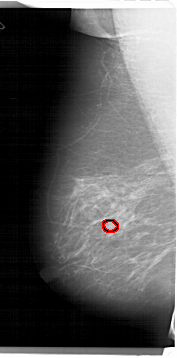

FILE: A_1335_1.LEFT_MLO.OVERLAY

TOTAL_ABNORMALITIES 1

ABNORMALITY 1

LESION_TYPE MASS SHAPE OVAL MARGINS OBSCURED

ASSESSMENT 3

SUBTLETY 3

PATHOLOGY BENIGN

TOTAL_OUTLINES 1

LEFT_MLO LINES 6796 PIXELS_PER_LINE 3361 BITS_PER_PIXEL 12 RESOLUTION 43.5 OVERLAY